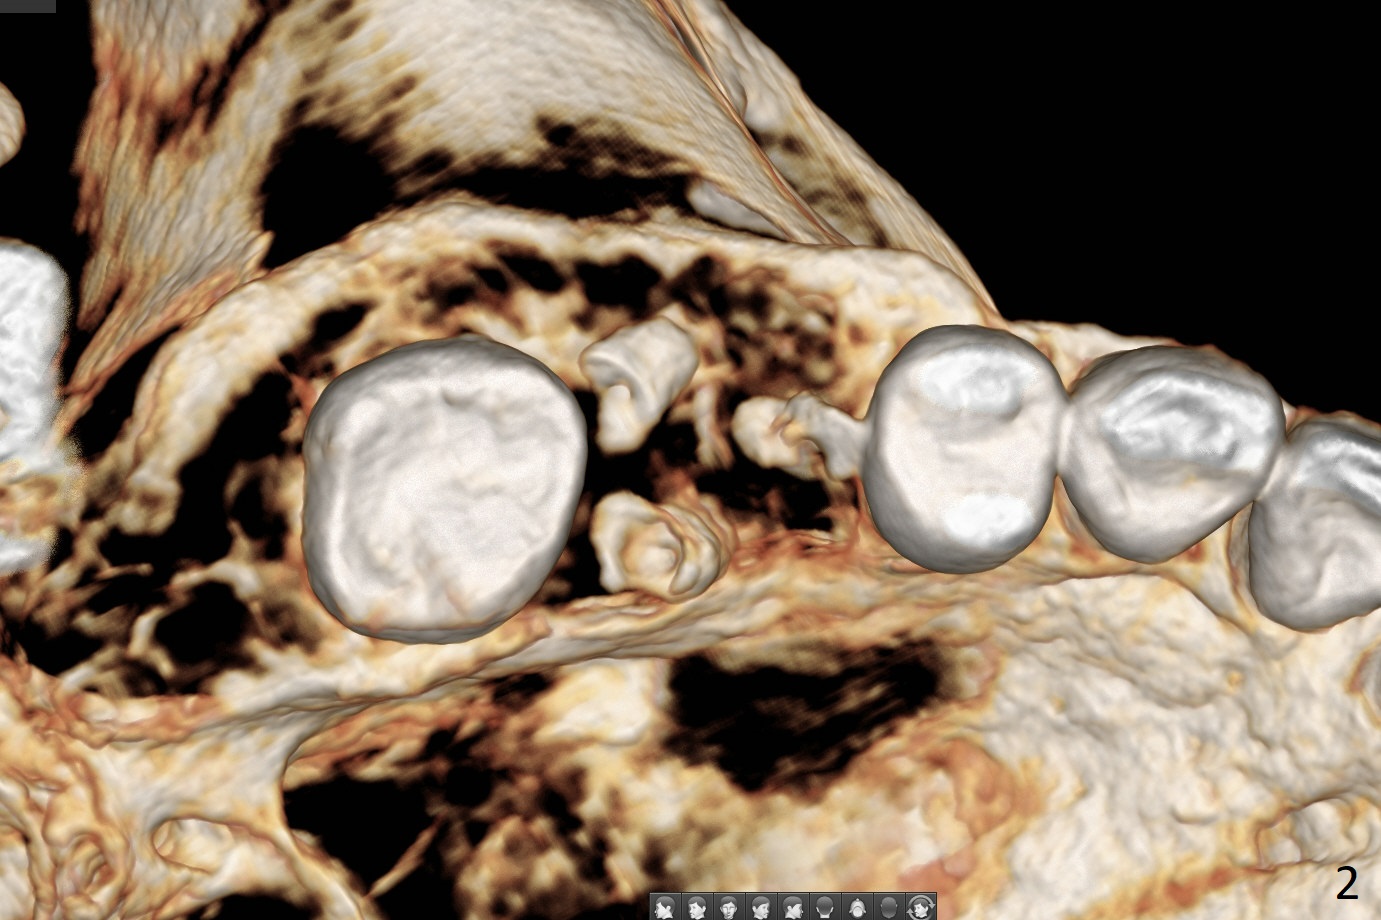

A 36-year-old woman is nervous about dentistry. She will take Valium by herselft before surgery (Fig.1). The tooth #3 has 3 residual roots (Fig.2 (CBCT 3 D occlusal view)). The bone is 2-3 mm thick (Fig.3,4 (sagittal, coronal sections)). A 5x7.3 mm implant will be placed with IS guide (Fig.5 (12 mm offset)). Since IBS implants are able to achieve amazing stability in the thin bone, prepare the shortest 4-5 mm in diameter dummy implants (IS (better surface treatment) and IBS) after sinus lift using UF Guided Sinus Lift Approach Kit (surgery). With intact tooth structure at #14, the bone height is not much (Fig.6), congenital (genetic) in nature. The infection at #31 is more severe (Fig.7). Extraction will be the 2nd in order. Because of limited bone, it is better to do bone graft first. The patient is concerned about the discolored upper right canine, which should be associated with orthodontics 20 years ago (take photos). The apical canal is obliterated (Fig.8,9 arrow) with periapical radiolucency (arrowhead). In fact the bone at #31 is so little that the tooth will be extracted for socket preservation.